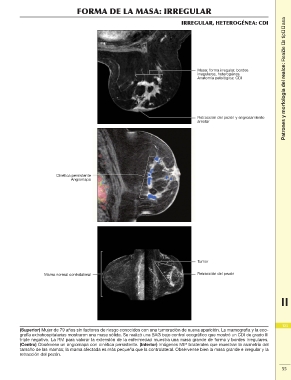

IRREGULAR, HETEROGÉNEA: CDI

Masa: forma irregular, bordes

irregulares, heterogénea

Anatomía patológica: CDI

Retracción del pezón y engrosamiento

areolar

Cinética persistente

Angiomapa

Mama normal contralateral Tumor

Retracción del pezón

(Superior) Mujer de 79 años sin factores de riesgo conocidos con una tumoración de nueva aparición. La mamografía y la eco- 123

grafía extrahospitalarias mostraron una masa sólida. Se realizó una BAG bajo control ecográfico que mostró un CDI de grado III

triple negativo. La RM para valorar la extensión de la enfermedad muestra una masa grande de forma y bordes irregulares. 2

(Centro) Obsérvese un angiomapa con cinética persistente. (Inferior) Imágenes MIP bilaterales que muestran la asimetría del

tamaño de las mamas; la mama afectada es más pequeña que la contralateral. Obsérvense bien la masa grande e irregular y la 55

retracción del pezón.